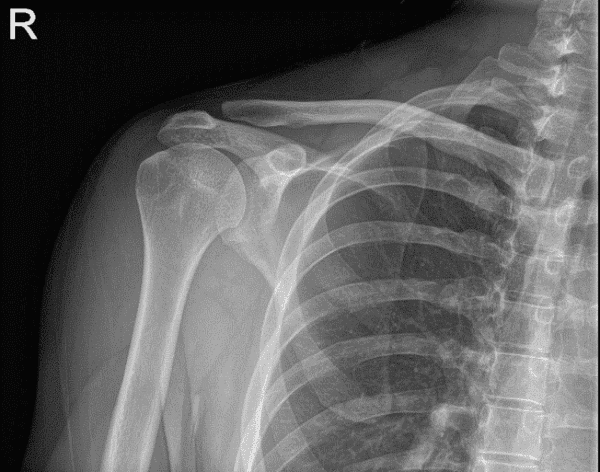

Bilateral Shoulder X-ray AP External and AP Internal

A 30-year-old patient visited our office with complaints of left collar bone pain. He was snowboarding, he was doing a jump and landed badly causing injury to his collarbone. He went to a hospital in CT where he was evaluated and x-rays were taken. He was discharged with a sling.

The severity of the pain was mild, when he was resting, when he was moving it. He denies any numbness or tingling. He presented results of x-ray which showed status post internal fixation with plate and screws of the left clavicle.